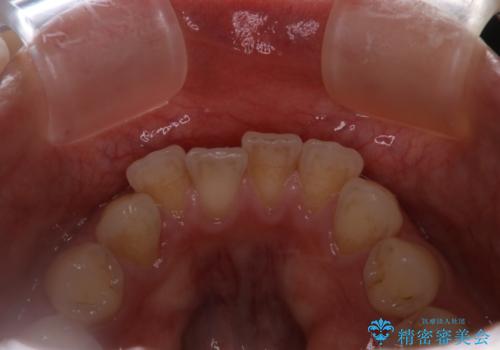

インビザラインのアタッチメントをつける前にPMTC

- インビザラインでの矯正治療中で、アタッチメントの設定前にきれな状態にしたいとのことでした。PMTC30分コースを行いました。

マウスピース矯正インビザライン治療では、歯の表面にアタッチメントという突起を設定します。(アタッチメントは歯の動きを効率的に移動するためのものです)

アタッチメントの設定時に、プラークや歯石・着色がついていると精密に付かないことや、外れやすくなることがあります。

PMTCを行い、専門的な機械でしっかりと汚れを除去してからアタッチメントの設定をすることがおススメです。